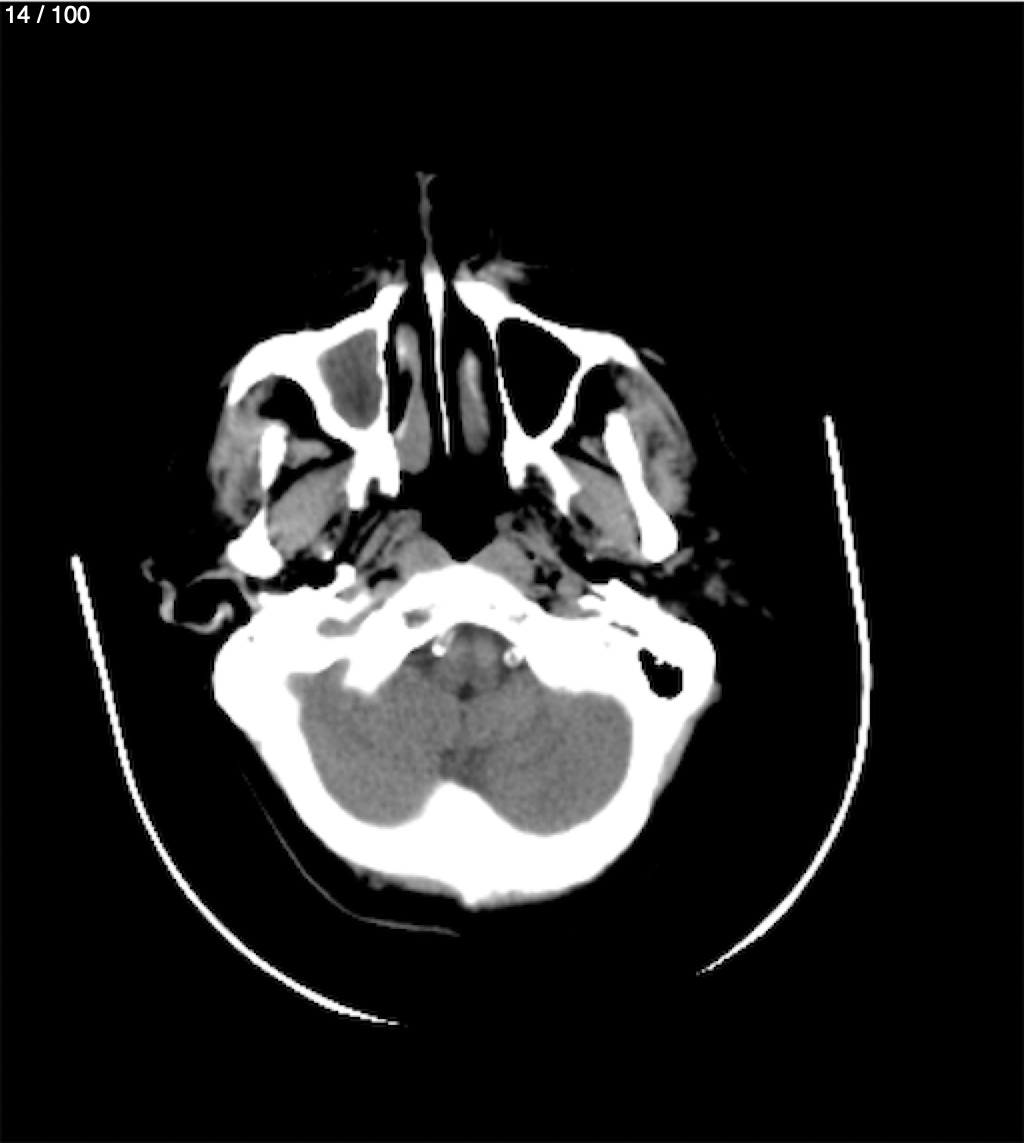

Valentin Perez Gomez 69A - T.C Craneo